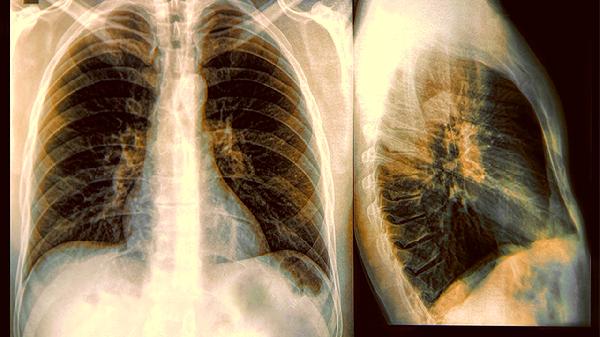

肺大疱是肺泡结构破坏后融合形成的薄壁气囊,常见于长期吸烟或慢性阻塞性肺疾病患者,胸部CT可见边缘清晰的低密度影。这类病变可能伴随咳嗽、活动后气促等症状,需避免剧烈运动以防破裂。支气管扩张则因气道反复感染导致永久性扩张,囊腔多沿支气管走行分布,典型症状为大量脓痰和反复咯血,急性发作期需使用盐酸氨溴索口服溶液等祛痰药物。肺气肿的囊腔由肺泡壁破坏融合形成,常见肺野透亮度增高和膈肌低平,稳定期可通过噻托溴铵粉吸入剂控制症状。

部分特殊感染如肺孢子菌肺炎也可形成弥漫性囊腔,多见于免疫功能低下人群,需通过复方磺胺甲噁唑片进行病原治疗。先天性肺囊性腺瘤样畸形是婴幼儿期罕见的发育异常,CT表现为蜂窝状多房囊腔,确诊后需手术切除。囊腔若合并实性成分或快速增长,需警惕肿瘤性病变可能。